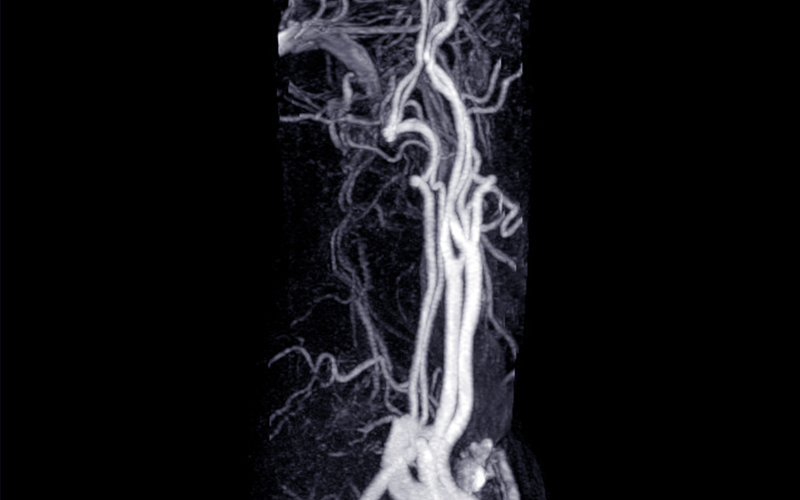

Trigeminal Neuralgia is one of the most painful neurological disorders, often described as sudden, electric shock-like pain on one side of the face. The condition results from compression of the trigeminal nerve by an abnormal blood vessel near the brainstem, which irritates the nerve and triggers severe pain even with mild touch or routine activities such as brushing or eating.

After confirming the diagnosis through MRI and clinical assessment, Dr. Rahul Gupta performs Microvascular Decompression using a minimally invasive approach. A small incision is made behind the ear to access the trigeminal nerve. Under high magnification, the offending blood vessel (usually an artery or vein) is gently separated from the nerve, and a tiny Teflon sponge is placed between them to prevent further contact.